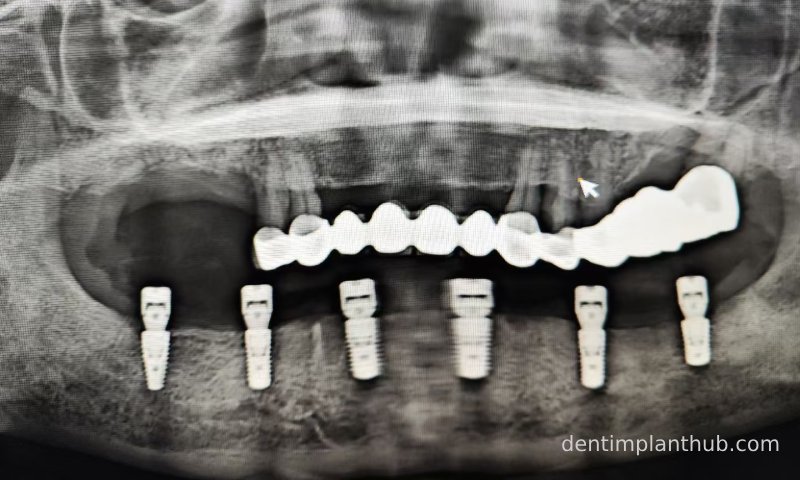

X-ray review panoramic film after surgery on 17/10/23